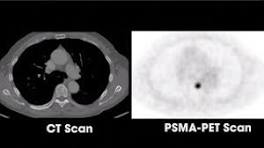

UCSF, UCLA Gain FDA Approval for Prostate Cancer Imaging Technique Their findings indicate that PSMA PET should be strongly considered both before initial treatment in men with high-risk cancers and in cases of cancer ...